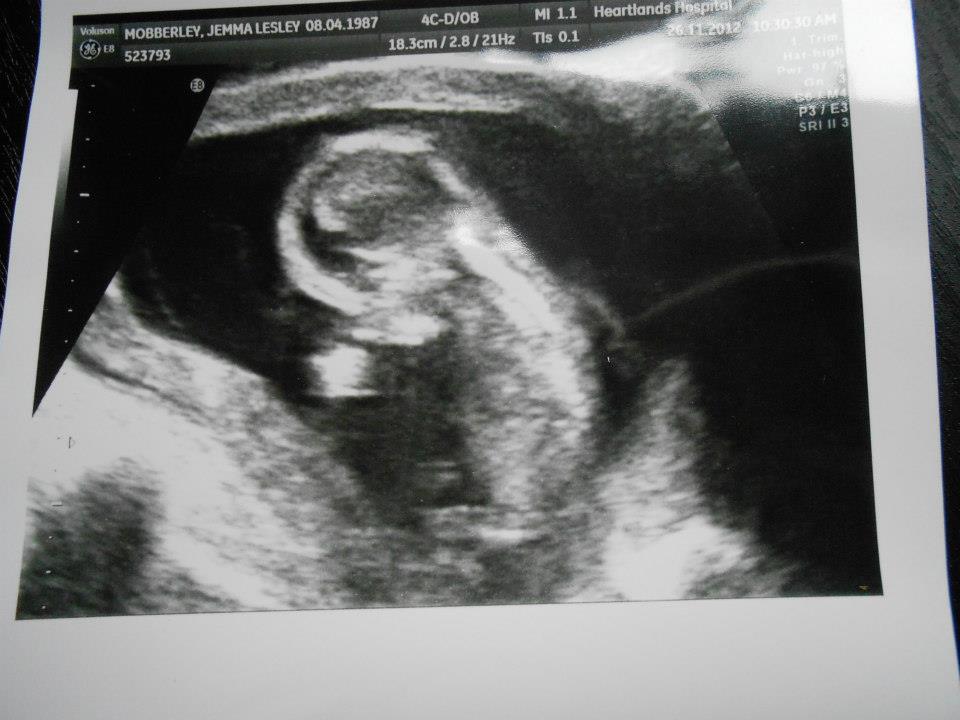

Just had my first scan and they couldnt see the sex im 14 weeks 2 days what would anyone guess. baby is sat up in pictureAttachment 6704

Sorry no guess here, no gender clues. Cute bub!

Im not sure, skull looks nice and round.

Looks like a little boy to me iv got two gills and three boys all my boys scan they had wee round shaped head my girls had pointer shaped heads ,thats my guess !!:-)

There is no nub shot and when the baby is sitting up I don't think it is accurate anyway.

I agree with the last poster, my boys all had round skulls and this time I could see it was different straight away cause it is pointy, I don't know if that is a theory or not, but an observation.

Hard to tell. I wish we had a better picture to guess!